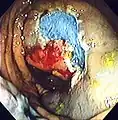

Colonoscopy (/ˌkɒləˈnɒskəpi/) or coloscopy (/kəˈlɒskəpi/)[1] is a medical procedure involving the endoscopic examination of the large bowel (colon) and the distal portion of the small bowel. This examination is performed using either a CCD camera or a fiber optic camera, which is mounted on a flexible tube and passed through the anus.[2][3]

The purpose of a colonoscopy is to provide a visual diagnosis via inspection of the internal lining of the colon wall, which may include identifying issues such as ulceration or precancerous polyps, and to enable the opportunity for biopsy or the removal of suspected colorectal cancer lesions.[4][5]